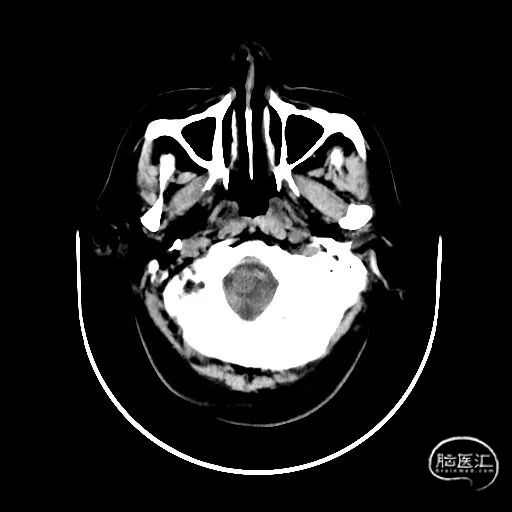

颅脑CT:未见明显缺血/出血病灶。

CTA提示:右侧椎动脉纤细,左侧椎动脉V1、V4段纤细。

MRI提示小脑缺血性改变。

术后CT:未见明显脑出血,双侧小脑低密度影。